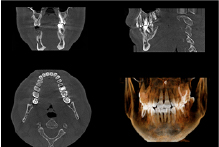

最初にインプラントが必要な歯の数、患者様の骨がどのような状態にあるのかを診察し治療方針を決定します。その後手術で埋め込んだネジが骨にくっつくのを3ヶ月位待ちます。